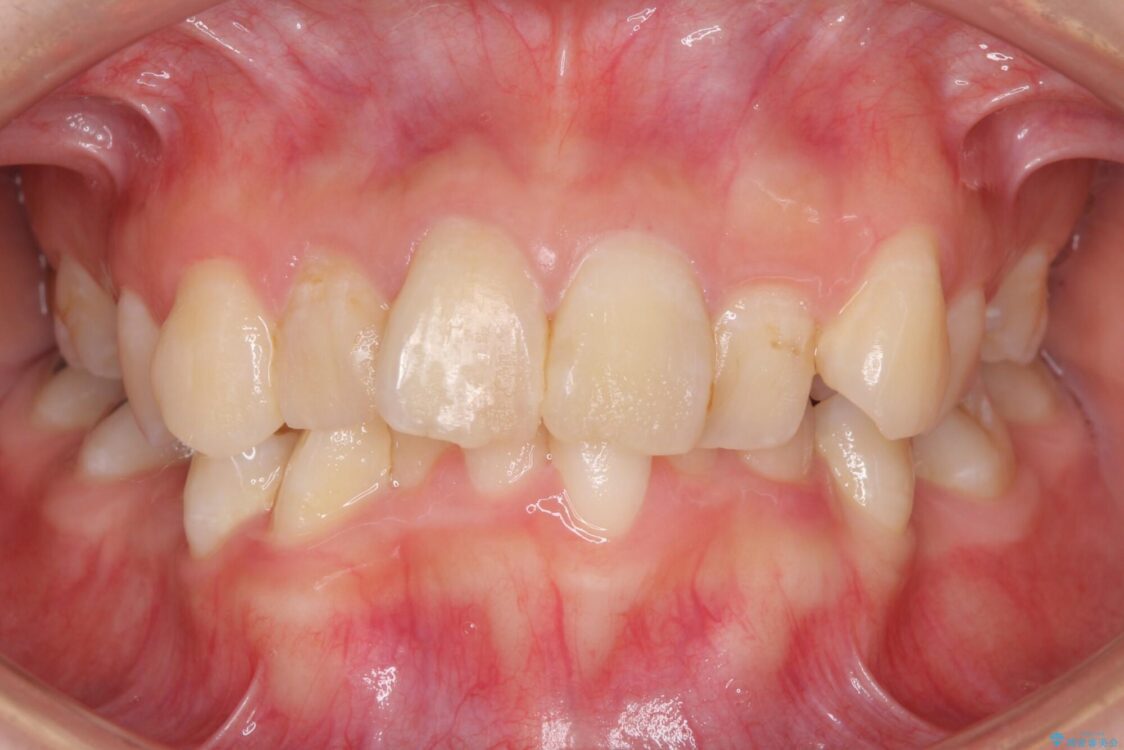

治療前

• デコボコと深い咬み合わせ ワイヤー装置での抜歯矯正 治療前画像

内側に倒れ込んだ歯や下の前歯が隠れてしまうほどの咬み合わせを改善したいとのことで来院された患者様です。

下顎の叢生を解消するために抜歯が必要であり、奥歯の咬み合わせや口元の印象から、上顎も同様に抜歯と判断し、上下左右の第1小臼歯4本抜歯してワイヤー装置にて矯正治療を行うこととしました。